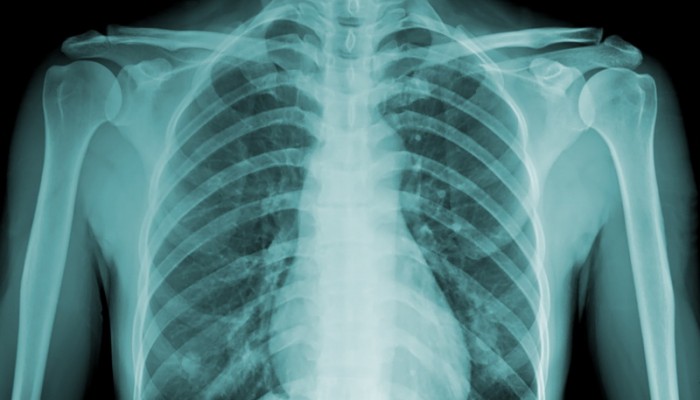

Рентген грудной клетки, в отличие от многих лабораторных и инструментальных исследований, практически не требует специфической подготовки. Достаточно лишь явиться в необходимый кабинет, где лаборант даст необходимые рекомендации:

- Сначала нужно раздеться до пояса, чтобы лишние слои одежды не препятствовали прохождению рентгеновских лучей. Так как ткань может иметь разную плотность, то на снимке возникнут грубые помехи.

- Также рекомендуется снять любые металлические предметы, которые будут сильно отражать рентгеновские лучи. К ним относятся различные ювелирные изделия – цепочки, крестики. Женщинам требуется проводить исследование без бюстгальтера.

- Затем человек располагается грудью к специальному экрану, высота которого регулируется индивидуально. Подбородок необходимо положить на пластмассовое ложе, находящееся на уровне головы.

- После этого требуется развести лопатки – для этого пациента просят свести плечи либо взяться за рукоятки, находящиеся по бокам от экрана. По команде лаборанта нужно сделать глубокий вдох, и задержать дыхание.

- В это время излучение проходит через все слои тканей, создавая следы на плёнке, расположенной спереди. После проявления снимок готов, что позволяет рентгенологу полностью описать его.

В некоторых случаях рентгенография грудной клетки выполняется в дополнительных проекциях – для этого исследуемого просят повернуться к экрану боком, и завести руку за голову.